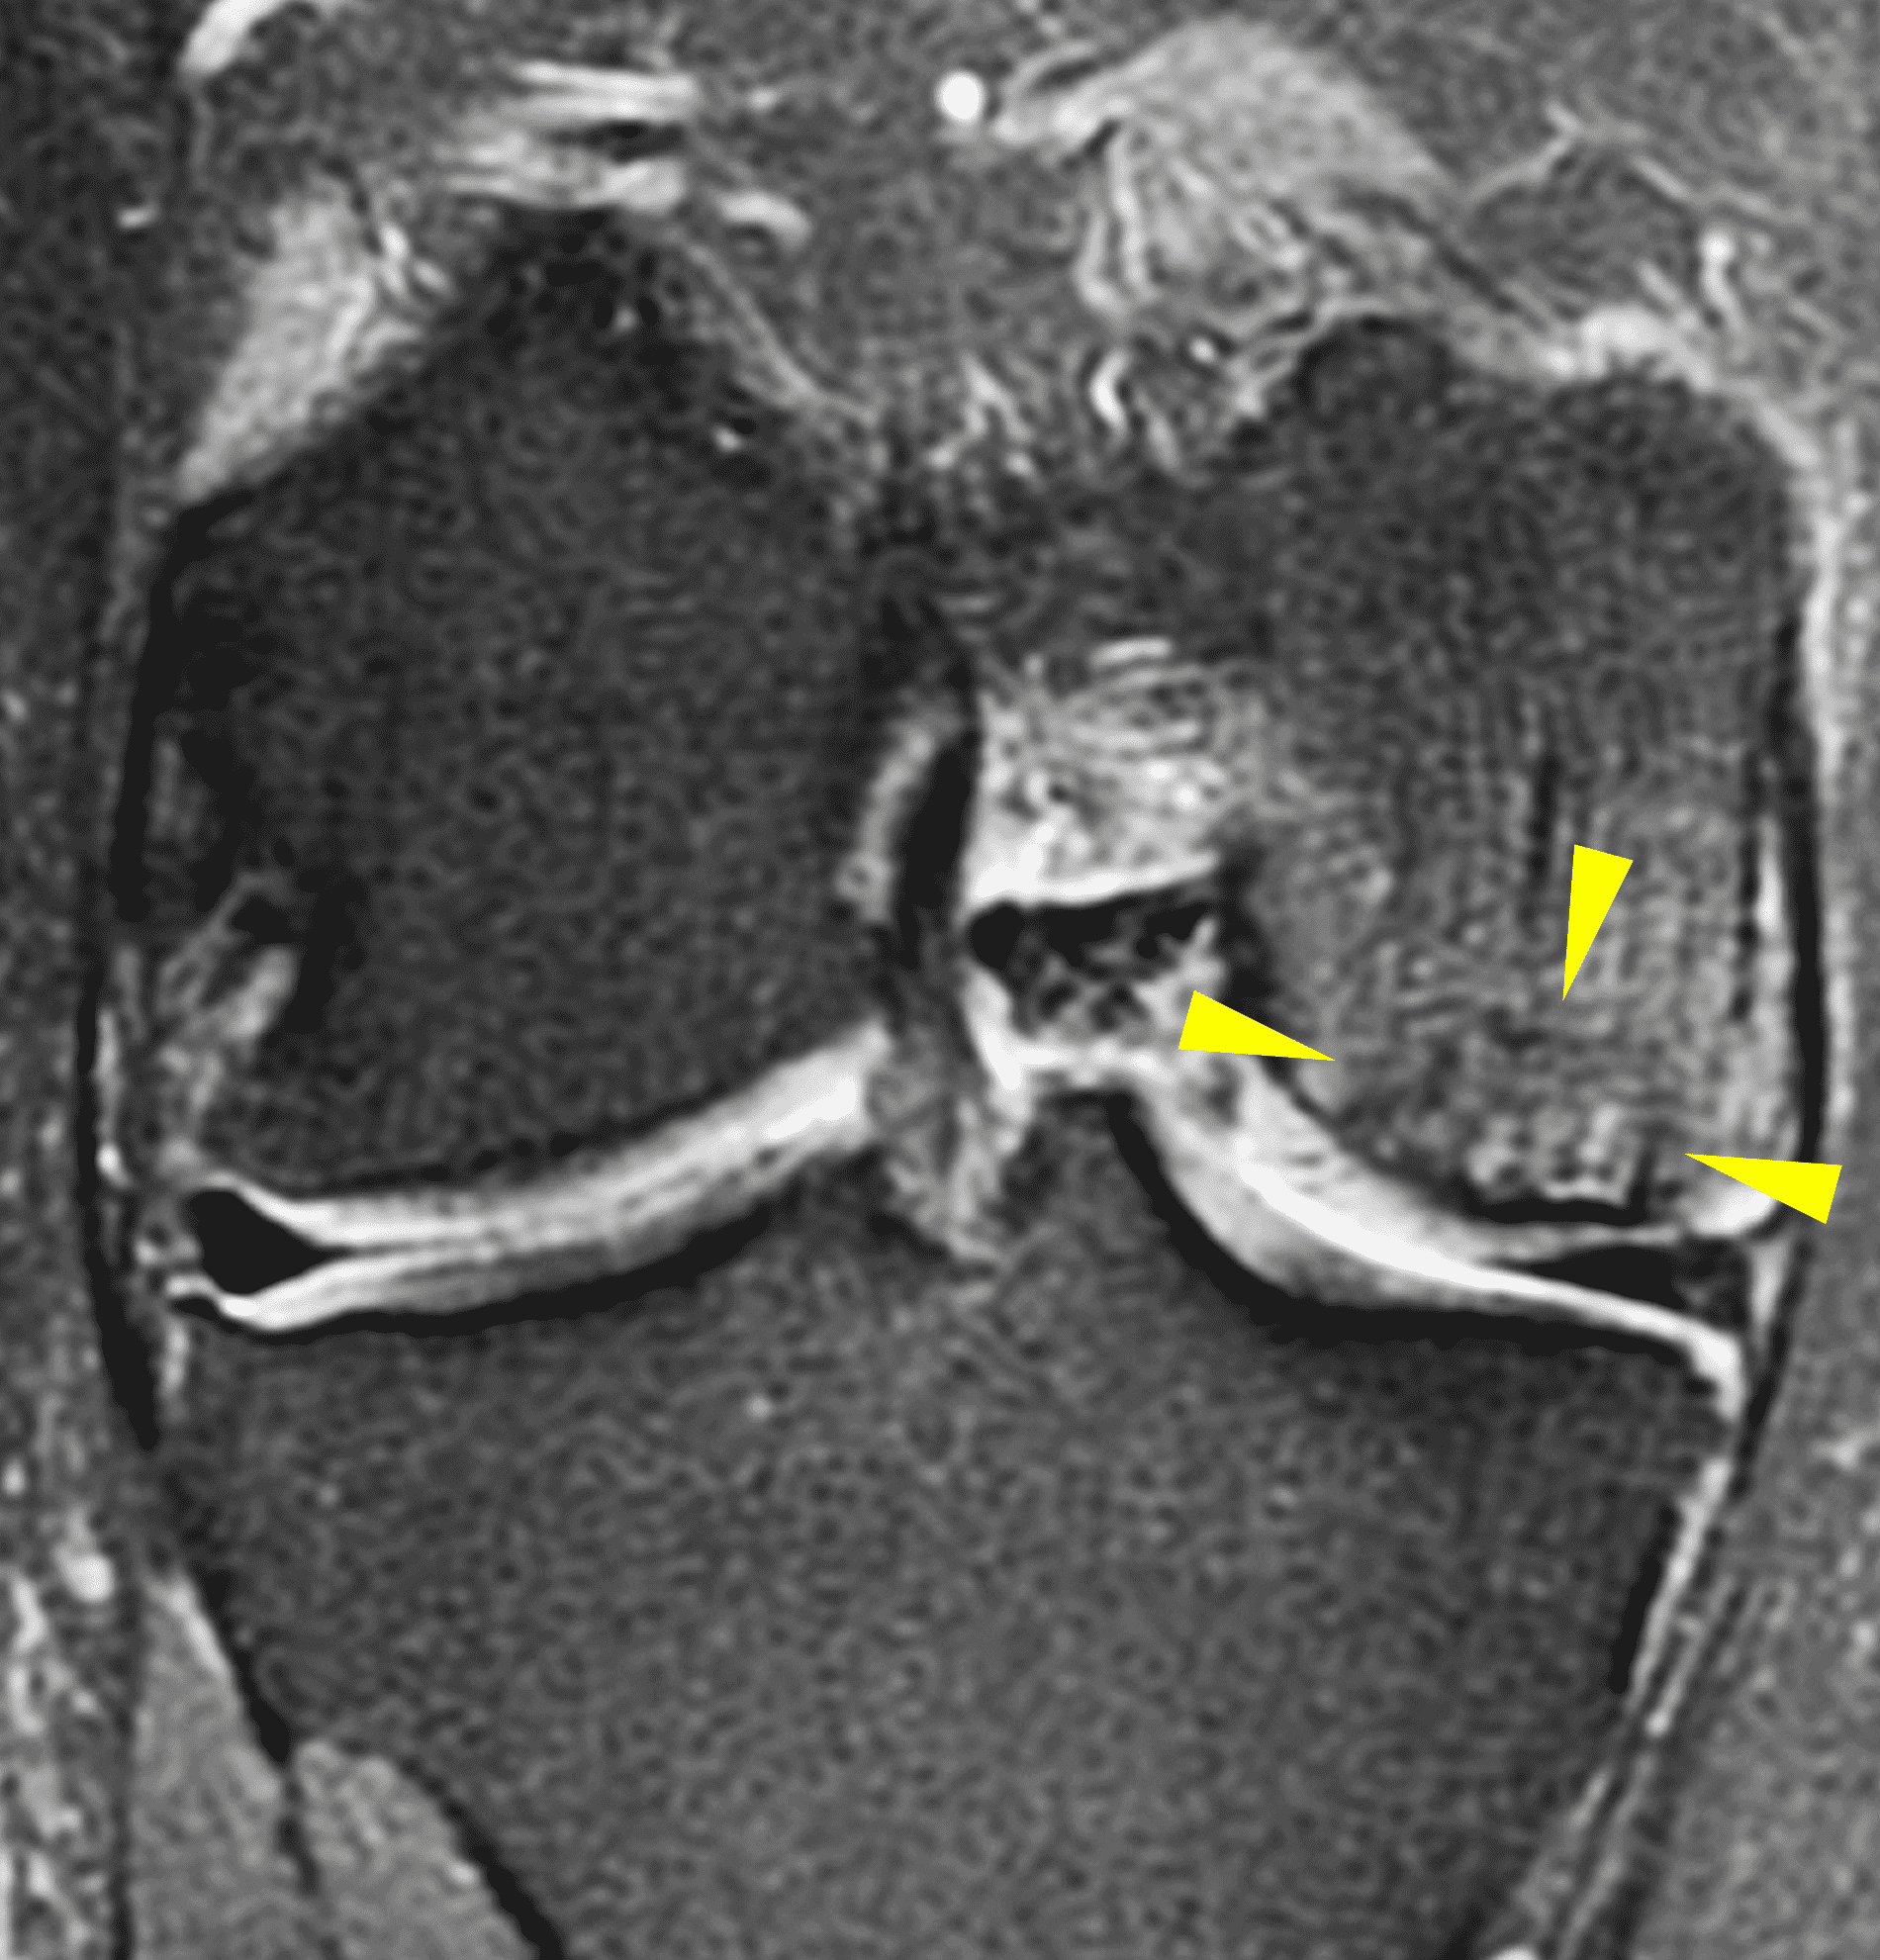

A 32-year-old man suffered a traumatic chondral injury to the medial femoral condyle that was treated with an osteochondral allograft 20 months previously. Representative images from a current knee MRI include (1A) coronal fat-suppressed fluid-sensitive and sagittal (1B) T1-weighted, (1C) proton density-weighted, and (1D) T2-weighted sequences. Are the post-operative MRI findings normal and expected, or abnormal and pathologic? Based on these images, would you characterize the procedure as a success or failure?

Figure 2: (2A) On the coronal image, the margins of the osteochondral graft are faintly visible (arrowheads). Both the graft and underlying bone show mild marrow edema, an expected finding. (2B) The T1-weighted image shows continuity of the marrow in the graft (asterisks) with the underlying bone, indicating osseous integration. A bioabsorbable pin (arrow) used for graft fixation is partly visible. (2C) The proton density-weighted image shows a low signal intensity seam (black arrow) between the native cartilage and transplant, as well as a defect in the subchondral bone plate of the graft (red arrow) where the pin was drilled, both normal findings. (2D) The T2-weighted image shows a smooth, congruent articular surface (arrows), restoring the normal anatomy, and a tiny subchondral cyst. No findings are present to suggest graft failure. The patient’s current symptoms were attributed to pathology elsewhere in the joint (not shown).

Successful osteochondral allograft procedure.

The postoperative imaging appearance of osteochondral allografts is similar to autografts (Figure 2).33 The subchondral bone plate of the donor and recipient sites do not have to match, but the articular surface should be congruent. Grafts that fail to incorporate by one year have a poor prognosis. Persistent marrow edema (beyond 12 months), a thick graft interface containing cysts or fluid, and subsidence of the graft are associated with poor osseous healing and worse outcomes. Extensive host marrow edema and severe synovitis may be a clue to immunologic rejection of the graft (Figure 18).21, 34